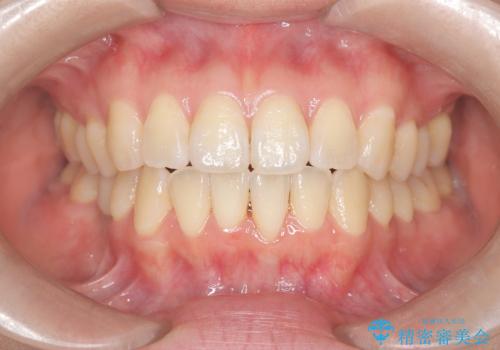

下顎前歯の叢生が整い、右下5番部には機能的かつ審美的なインプラント補綴が完了しました。

咬合全体のバランスも改善し、長期的な安定性が期待される状態となりました。

患者様にも「長年気になっていた前歯のがたつきも一緒に治せてよかった」と喜んでいただけました。